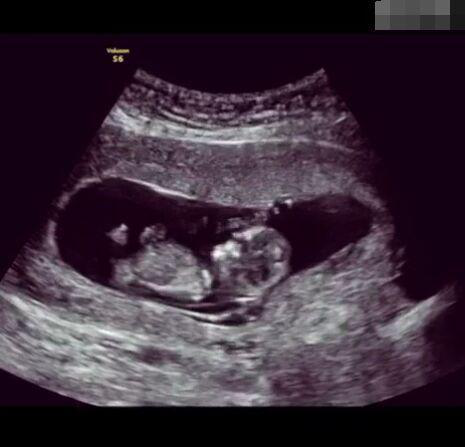

懷孕后,寶寶的性別一直是全家人的重點(diǎn)關(guān)注對(duì)象。而男女性別的差異,在基因?qū)用骟w現(xiàn)在第二十三對(duì)染色體上,如果是XY則是男孩,XX則是女孩,這都是由那枚與卵子結(jié)合的精子來決定。

圖片8.png

那些做了B超檢查確定胎兒男女,生下來后發(fā)現(xiàn)不對(duì)的,多半是因?yàn)樵贐超檢查時(shí)寶寶太調(diào)皮,以致影響了檢查準(zhǔn)確性。就比如說,有的女寶寶在媽媽肚子里玩自己的臍帶,把臍帶夾到了兩腿中間,B超就有一定幾率拍出來好像是男寶寶的特征,導(dǎo)致被誤認(rèn)為是男孩子。還有些男寶寶過分害羞,在做B超時(shí)雙腿緊緊并攏,醫(yī)生也很難判斷男女,只好大致猜測是女孩,就又造成了誤會(huì)。因此,B超亦不是萬能的。